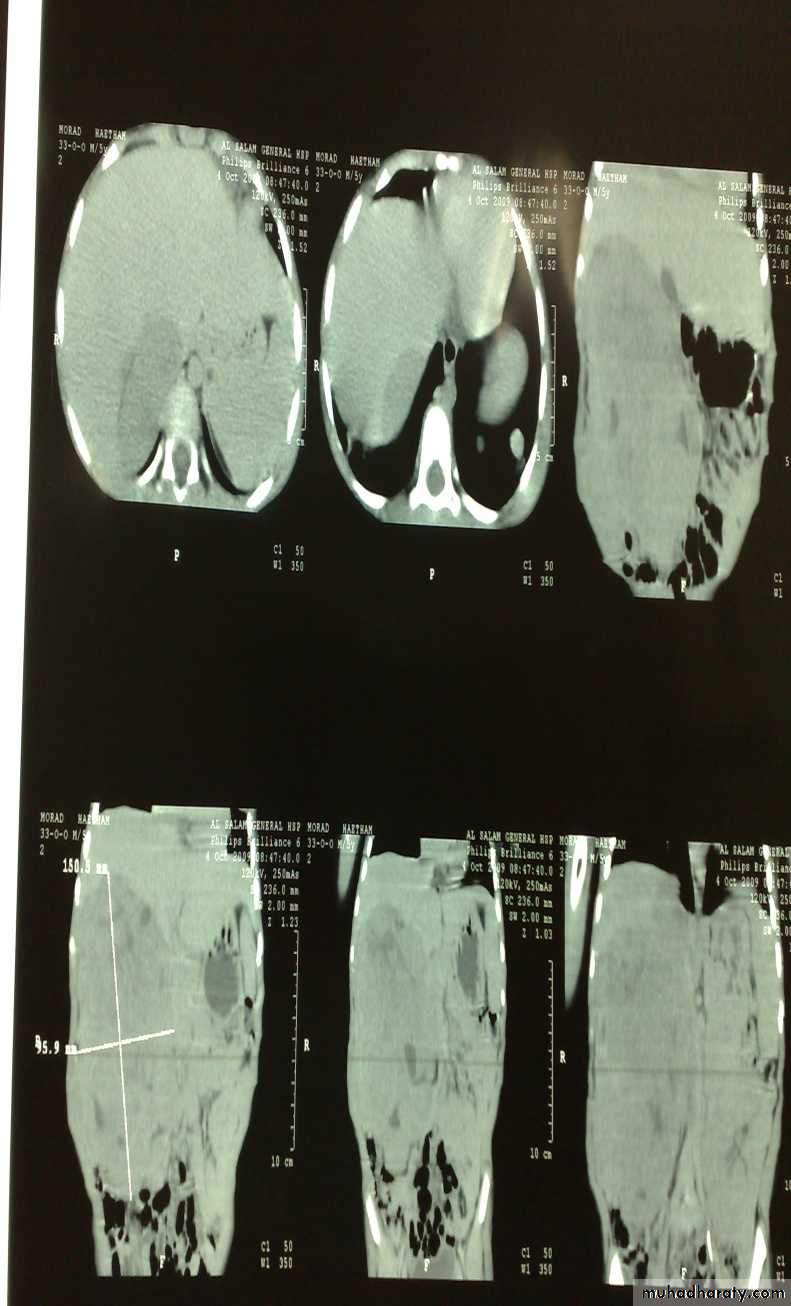

The Child with an Abdominal Mass